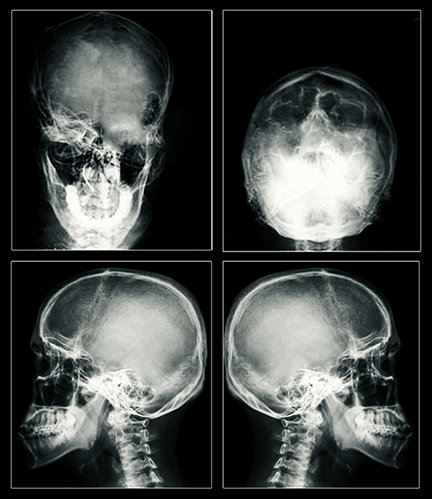

Le résultat reste le même : une crise de type grand mal, et des lésions cérébrales qui peuvent être permanentes. Aujourd’hui, le courant considérablement plus élevé peut créer des trous dans les cellules du cerveau et les détruire. L’électricité peut aussi détruire les cellules en produisant de la chaleur. L’IRM effectuée sur des patients victimes d’ECT, a révélé la présence de cicatrices et d’un rétrécissement du cerveau – preuve irréfutable de graves lésions.